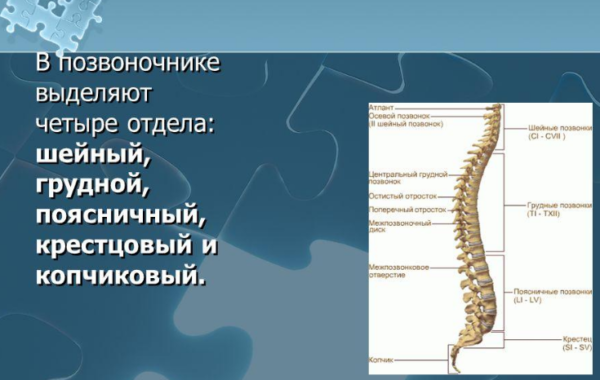

Формируется позвоночная конструкция из пяти зон или отделов. Название – по месту нахождения. В каждом из них свое количество позвонков, которые отличаются строением, размерами и другими параметрами, и сообщаются благодаря суставам и проходящим внутри связкам.

Отделы позвоночника

Шейная | Начало позвоночного столба, его верхняя часть, которая имеет выпукло-изогнутую форму и является самой подвижной зоной из пяти. Благодаря этому существует возможность наклона головы, поворотов и движений шеи. Состоит из семи позвонковых фрагментов, последний из которых считается пограничным и позволяет шейной зоне перейти в грудную. Позвонкам шейной зоны присвоено буквенное обозначение С и нумерация от 1 до 7. Первый представляет собой две дуги и служит опорой для черепа. Следующий тоже имеет нетипичное строение – спереди расположена ость, которая помогает вращаться первому позвонку. Отличается строением и седьмой, он является видоизмененным и служит проводником поперечной вены. Вся данная зона максимально близко расположена к мозгу, поэтому любые ее повреждения могут стать причиной летального исхода. |

Грудная | Это зона самая протяженная и насчитывает наибольшее количество сегментов. В ней 12 позвонков, обозначенных буквой Т (либо D) и нумерацией от 1 до 12. Форма дуги выгнутая в виде буквы С. К ней прикрепляются реберные пластины, и отдел является самым статичным. Ребра, служащие защитным каркасом для сердца и легких, не дают зоне совершать широкие наклонные движения. Повреждения в данной зоне вызывают болезни практически всего организма. |

Поясничная | В этой зоне позвоночных сегментов всего пять. Они представлены обозначениями L1 — L5 и являются самыми крупными. В этой части дуги существует плавный изгиб, который является соединительным «мостиком» грудной и крестцовой зоны. На долю поясничных позвонков приходится самая тяжелая работа. Они несут самую большую нагрузку, амортизируют все тело, выдерживают давление его верхней части и отвечают за любое движение (пространственное перемещение) – от ходьбы до прыжков и бега. Патологии, деформации, травмы чаще всего происходят именно в поясничной зоне. |

Крестцовая | Данную зону лишь условно считают состоящей из позвонков. Им тоже присвоен буквенный код – S, и нумерация от 1 до 5. Но на самом деле состоит зона из кости треугольной формы, которую образуют все пять позвонков, являющихся сросшимися. Кость соединяет таз и позвоночник, и отвечает за состояние бедренных костей, ягодиц и крестца. |

Копчиковая | Последняя нижняя зона обозначается Со и нумеруется 1-5. Но у каждого человека здесь может быть разное количество позвоночных сегментов – минимум три, максимум пять. Представляют собой они тоже сросшуюся кость в форме перевернутой пирамиды, которая к тому же имеет изогнутую форму. Орган является соединительным и опорным, транслируя нагрузку костям таза и распределяя ее. |